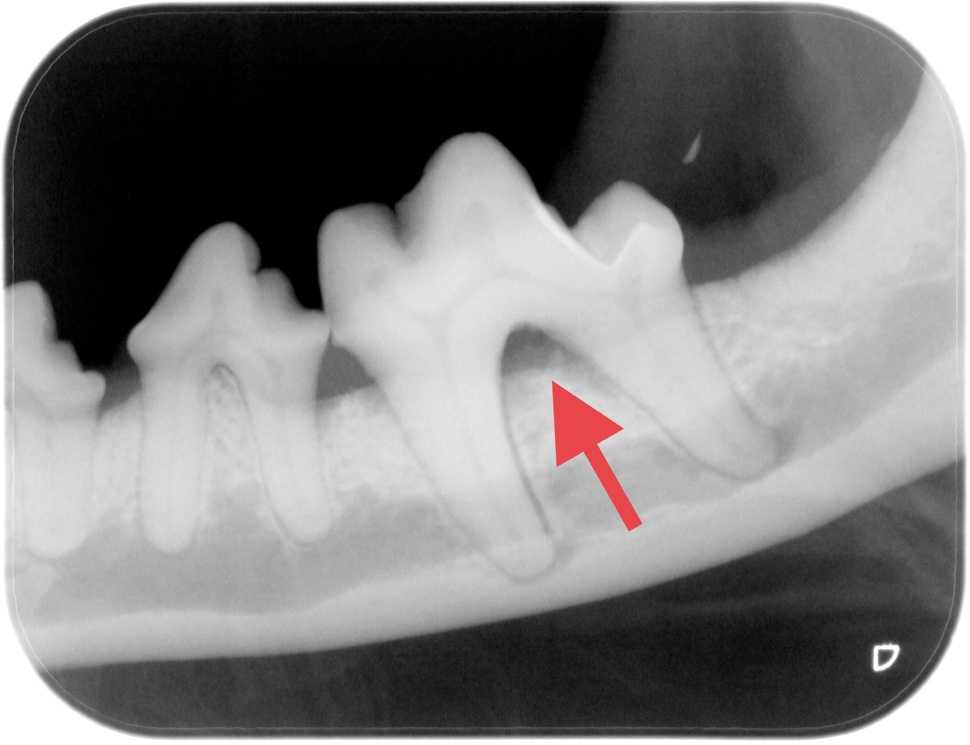

Dog & Cat Tooth Extractions When To Remove Walkerville Vet